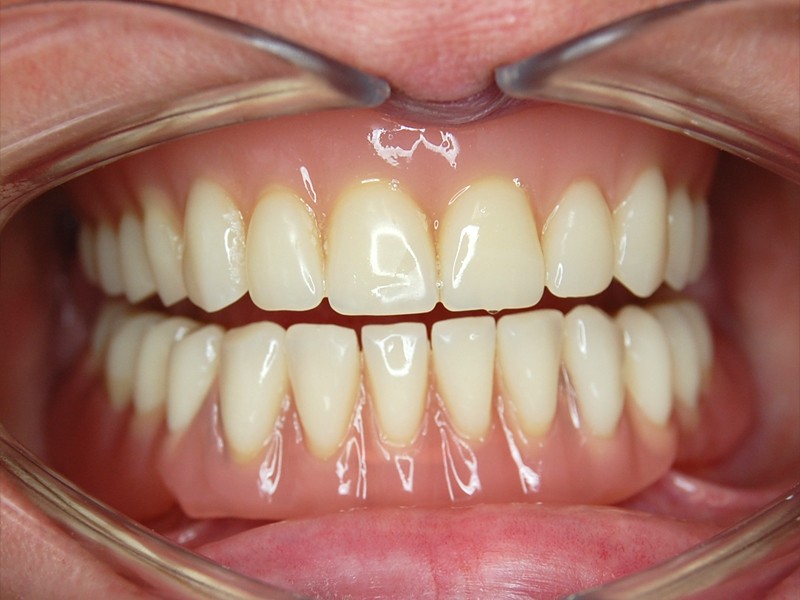

Subperiosteálny implantát je vytvorený presne na mieru . Nalieha priamo na povrch kosti a je väčšinou fixovaný mikroskrutkami. Do ústnej dutiny zasahujú len retenčné prvky pre uchytenie hybridnej snímateĺnej náhrady. Môže byť použitý v maxille aj mandibule.

Postup výroby spočíva v CT scane kosti, analýze, digitálnej výrobe 3D modelu kosti, individuálnom nadizajnovaní optimálneho tvaru subperiosteálneho implantátu, ktorý je vyrobený výhradne z bioinertného titánu najvyššej kvality grade 5. Finálny produkt je po povrchovej úprave inzerovaný operačne v lokálnej alebo celkovej anestéze. Pooperačné hojenie sliznice vyžaduje krátky čas ktorý využívame na zhotovenie hybridnej snímateĺnej náhrady podĺa náročnosti pacienta.